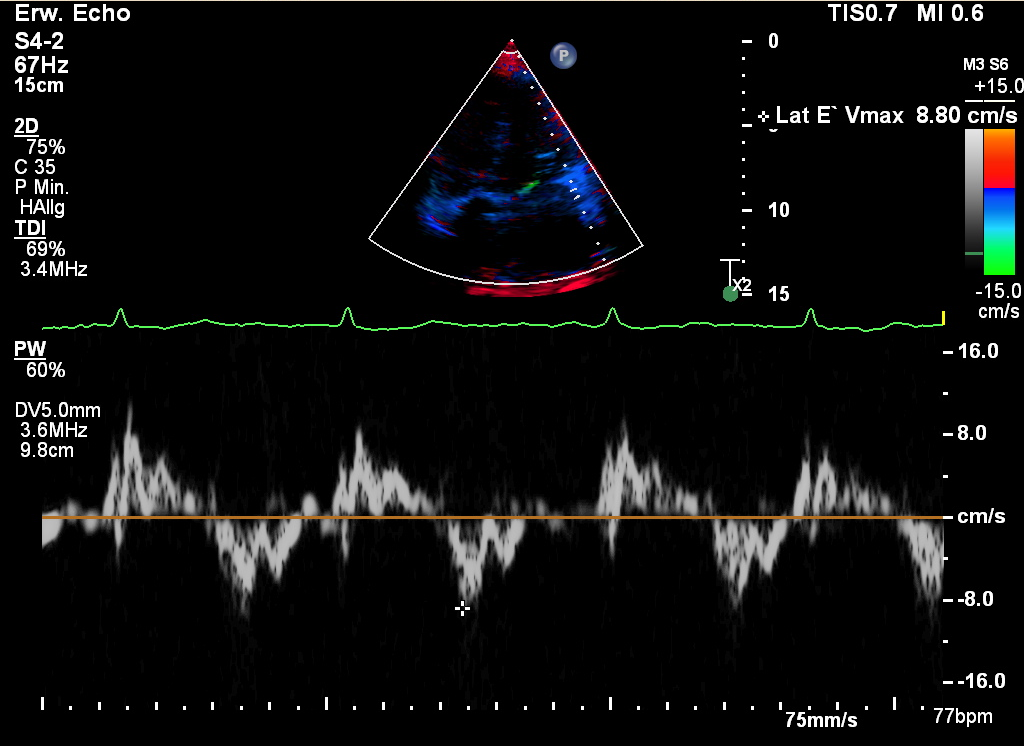

Gewebe-Doppler (tissue Doppler, TDI)

Gewebe-Doppler